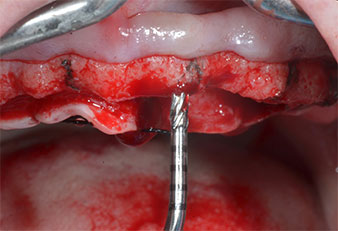

Wegen des relativ harten Knochens (D2) an den Positionen 11 und 21 wurden die 10 mm langen Implantatlager in diesem Bereich abschließend mit einem 4-mm-Spiralbohrer, dem chirurgischen Winkelstück WS-75 L von W&H und dem W&H Implantmed Implantologiemotor in Verbindung mit dem optionalen W&H Osstell ISQ module präpariert. Im Gegensatz dazu wurde der weiche Knochen der Implantatlager im Seitenzahnbereich mit dem Piezomed I3P auf den abschließenden Durchmesser von 3 mm erweitert. Die Implantate wurden dann transgingival eingesetzt, die Einheildauer betrug drei Monate (Abb. 6-10). Die vorhandene Prothese wurde auf vier provisorischen Implantaten abgestützt (Abb. 8).